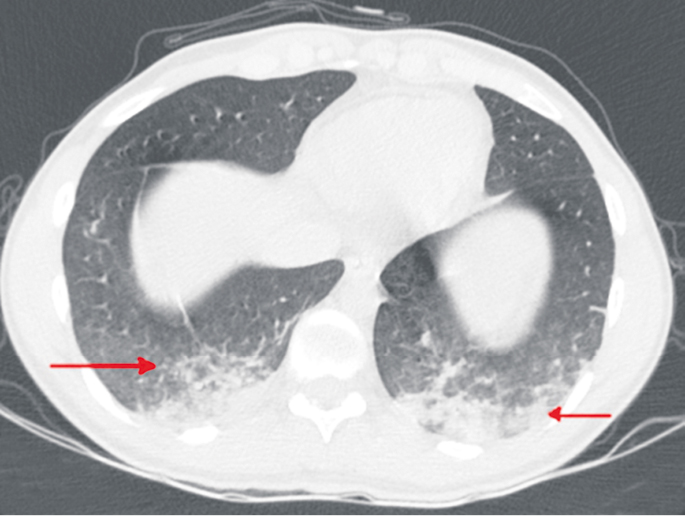

Также были выявлены дисметаболические нарушения в виде повышения уровня калия до 6 ммоль/л и незначительного снижения общего белка. При токсико-химическом исследовании биосред в моче были обнаружены следы 1,4-бензодиазепина и трамадола, что было связано с введением данных препаратов при интубации трахеи на предыдущем этапе оказания медицинской помощи. В первые сутки наблюдения была выполнена компьютерная томография (КТ) головы, груди, живота, таза, при которой определялись признаки сливной альвеолярной инфильтрации легочной ткани с преимущественным выполнением объема в задних базальных отделах обоих легких (рис. 4).

Рис. 4. КТ при поступлении (02.11.2021). Стрелками указаны признаки сливной альвеолярной инфильтрации легочной ткани с преимущественным выполнением объема в задних базальных отделах обоих легких

Fig. 4. CT at admission (02.11.2021). Arrows indicate signs of draining alveolar infiltration of lung tissue with predominant volume in the posterior basal sections of both lungs